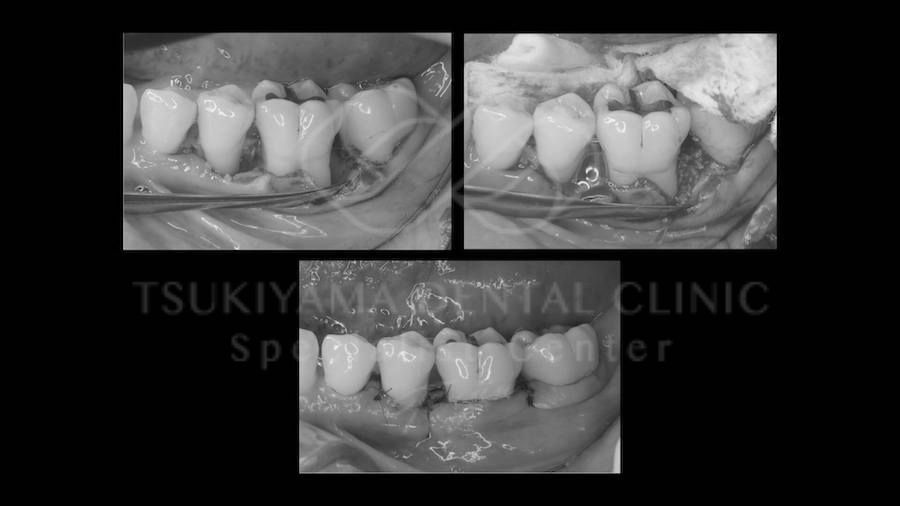

治療途中経過

この術式は大臼歯(だいきゅうし)と言われる奥歯に適応される処置です。

大臼歯には、歯の根っこが複数本ありますが、この大臼歯が重度歯周病におかされた際に複数本ある歯の根っこを意図的に分割して小さい歯として利用したり、より悪い根っこだけを抜歯したりして最終的にはその歯を温存する外科処置、修復処置になります。

頬側遠心根の歯根切除の症例